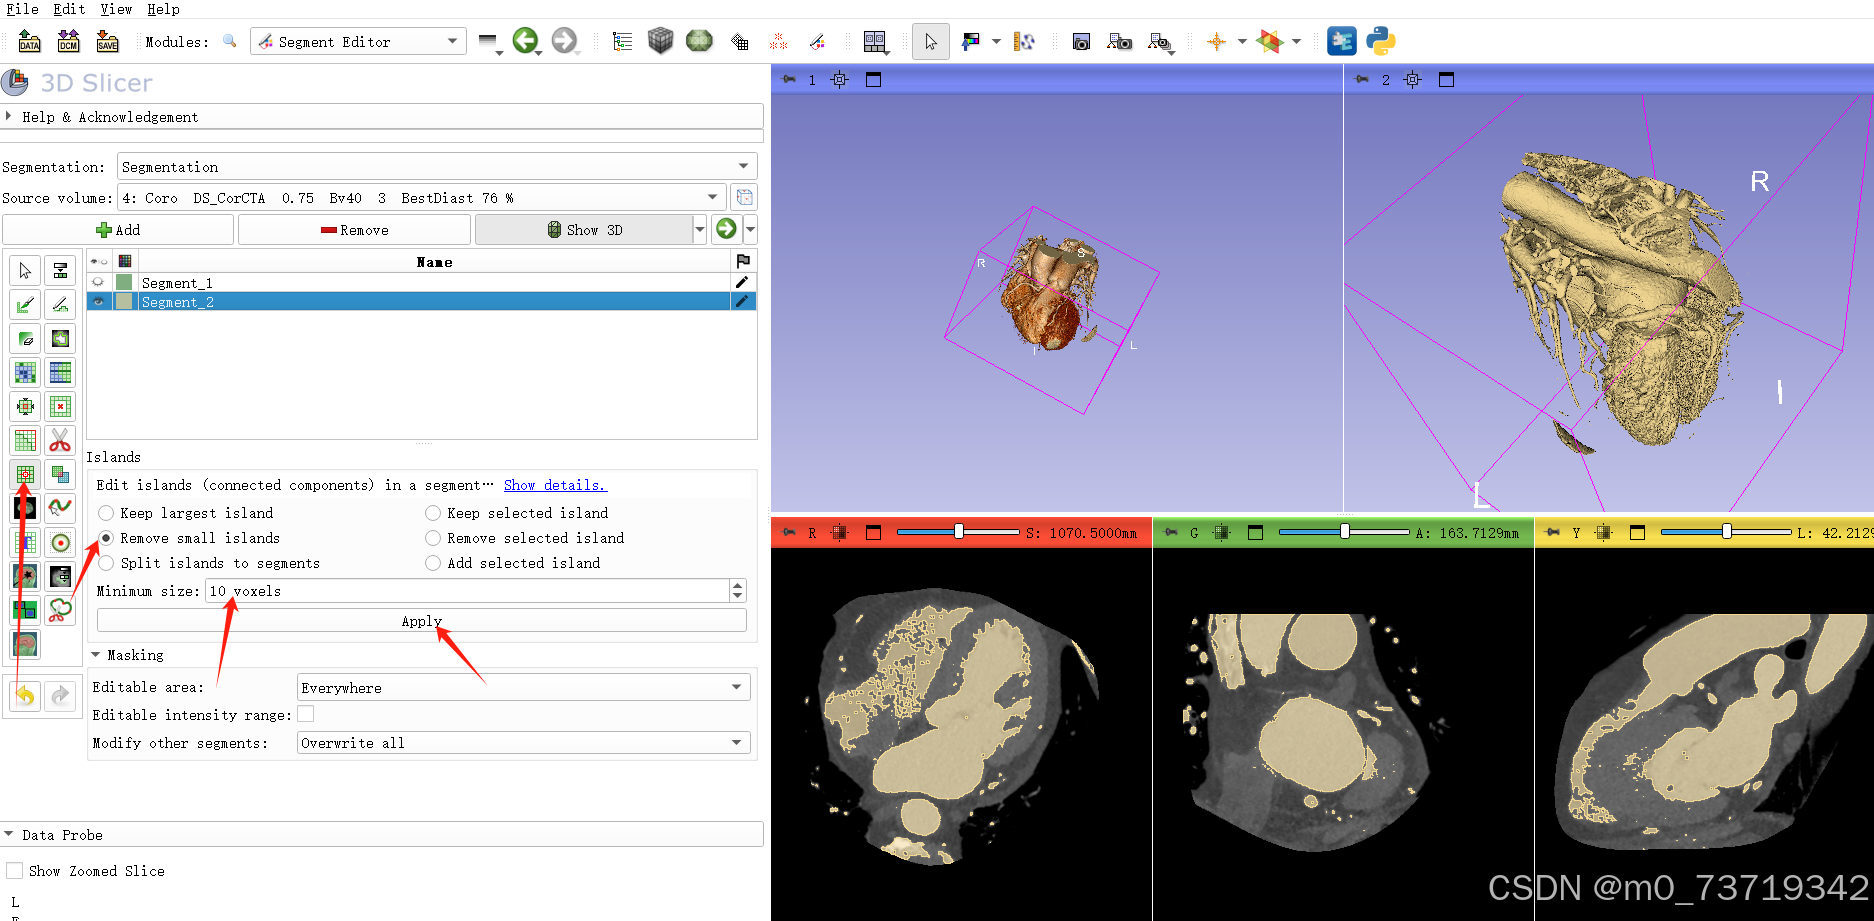

解决方法1:在标注之前先remove掉三维图像中的小噪点,显卡计算量减小,卡顿减轻